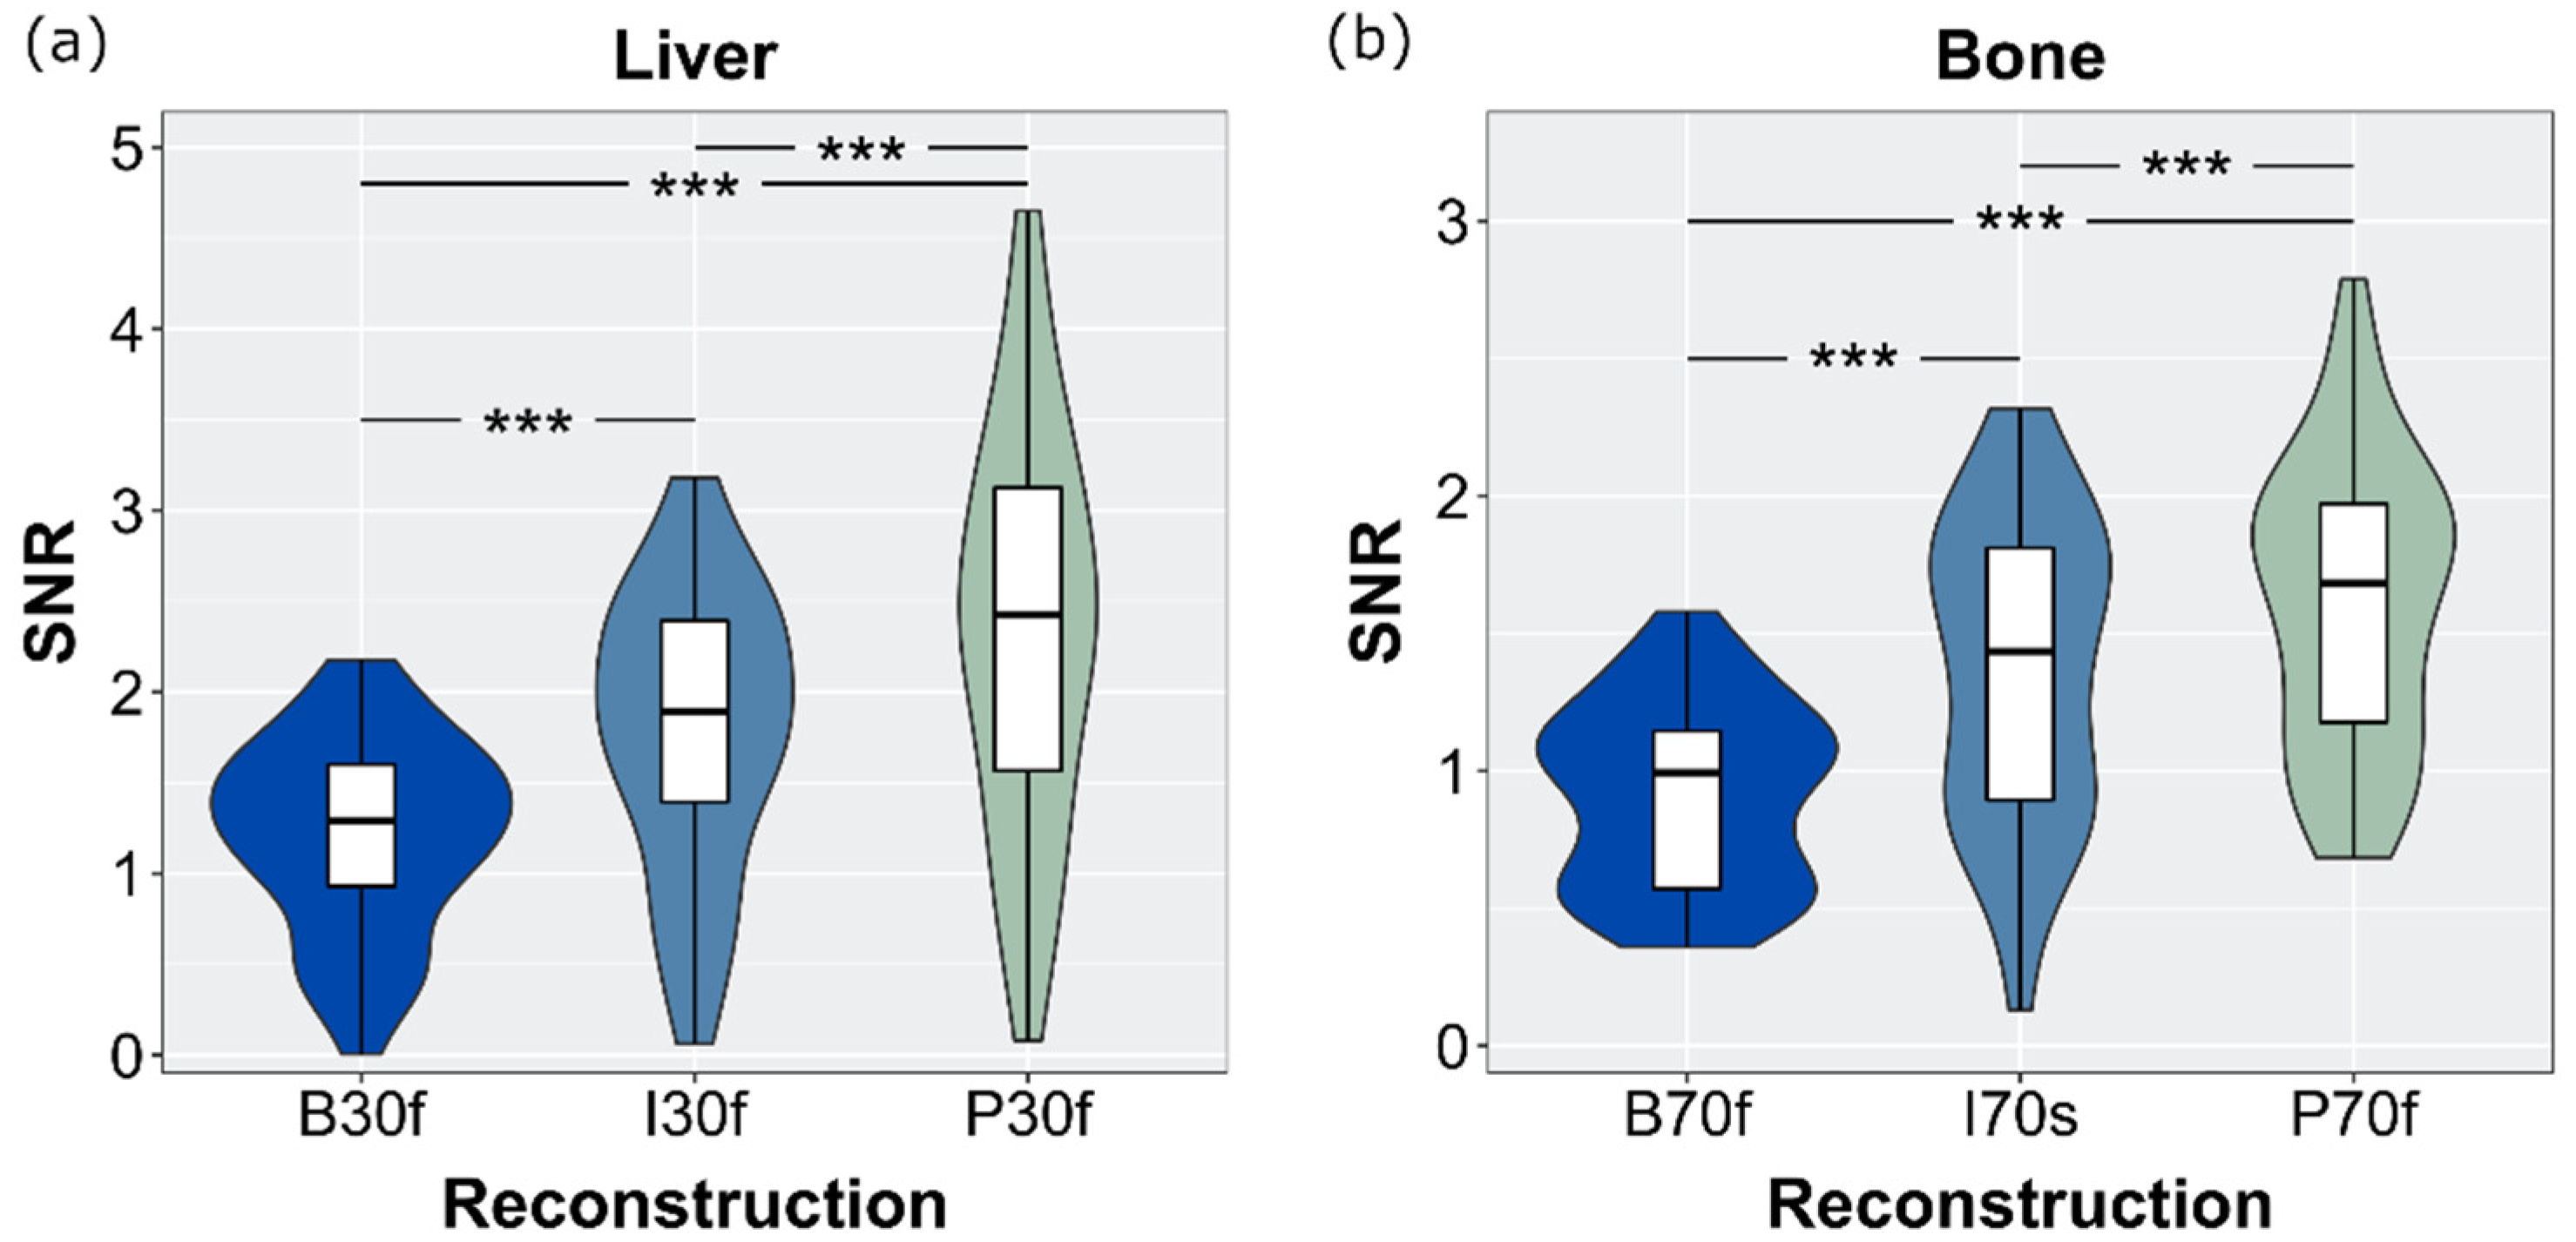

3.6. SNR and CNR

| Image Noise | B | I | P |

| Air (sharp) | 77.5 ± 15.9 | 49.4 ± 13.5 | 28.5 ± 14.3 |

| Bone (sharp) | 212.3 ± 40.1 | 143.0 ± 31.1 | 124.0 ± 20.7 |

| Liver (soft) | 38.2 ± 7.7 | 26.2 ± 5.0 | 20.3 ± 4.8 |

| Muscle (soft) | 31.6 ± 5.6 | 21.7 ± 3.9 | 14.5 ± 2.6 |

| Spleen (soft) | 34.5 ± 7.0 | 23.4 ± 4.8 | 16.4 ± 4.1 |

| Fat (soft) | 29.4 ± 5.6 | 20.4 ± 4.2 | 12.8 ± 3.1 |

| Statistical differences (p < 0.001) among all reconstructions within one ROI. Abbreviations: B: filtered back-projection, I: iterative reconstruction; P: PixelShine. | |||